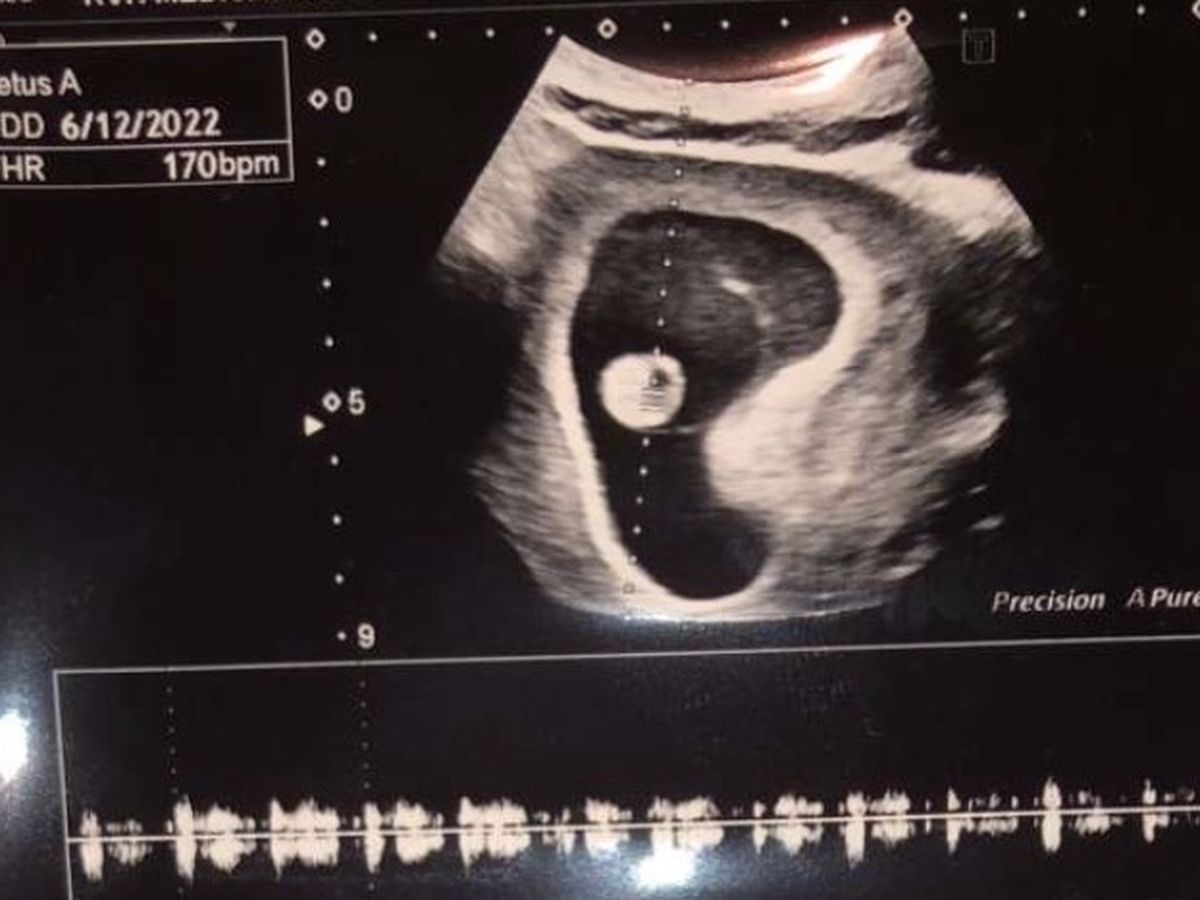

Hi, my name is Wendy. Tyler is my son, April is his soul mate. They found out they were pregnant six months ago. At first they were scared but they soon fell in love with the idea of a baby. They both wanted a little girl. When April was three months along they had the blood test done and checked for birth defects and gender. Little Hollow Lynn was confirmed. Tyler and April were so excited. They found a two bedroom apartment, and moved from their single apartment so Hollow would have her own room. They were so excited. They had a doctors appointment in which a 3D ultrasound was scheduled. By now April is six months along. Tyler sent me a picture of My granddaughters little foot. 30 minutes later he called me crying and I could hear April crying in the back ground. Hollow wasn’t going to live, she has or had Anencephaly. Which is where her sweet brain was exposed. She had no cranium covering her brain. Now April and Tyler are having to go and have surgery to remove Hollow since she is six months along. They will leave the hospital without their sweet baby girl. They are wanting her little hand and foot prints, but she will be cremated.